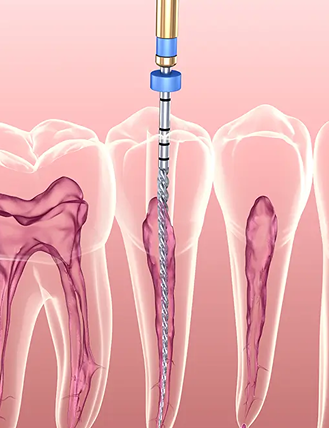

中文Endodontics

Save your tooth!

Endodontics comes to the rescue when you have tooth pain or infection caused by issues with the inside of your tooth. It involves procedures like root canal therapy that can save your tooth from being pulled out, allowing you to keep your natural teeth and avoid gaps in your smile.

Dental Microscope

Provides high-quality magnification and illumination, helping endodontists visualize the internal anatomy of teeth more clearly and precisely while treating complex root canal anatomy.